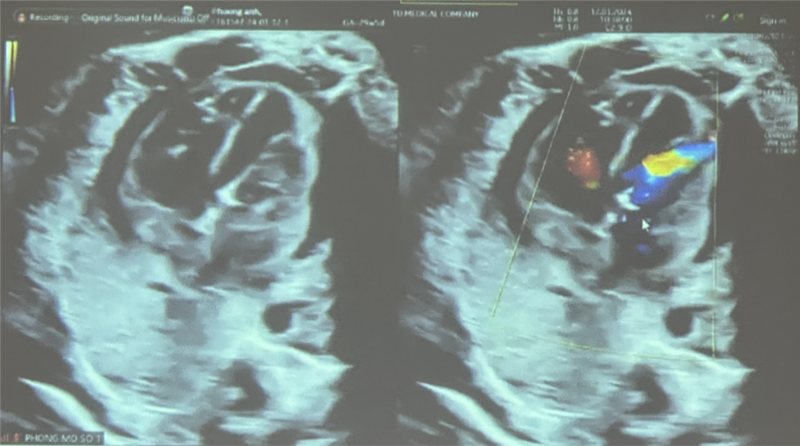

Đến ngày 11/1, thai được 29 tuần với diễn tiến hẹp van động mạch chủ nặng, đường kính van 2.6 mm, vận tốc máu qua van động mạch chủ 300cm/s, gây thiểu sản thất trái nặng hơn, trào ngược van 2 lá mức độ nặng.

Sau nong, kiểm tra dòng chảy qua van động mạch chủ lên tốt. Siêu âm kiểm sau thực hiện can thiệp, luồng thông PFO shunt phải – trái, vận tốc qua van động mạch chủ 180 cm/s, không ghi nhận hở chủ, nhịp tim thai 188 lần/phút, có tràn dịch màng ngoài tim nhẹ 4,5 mm.